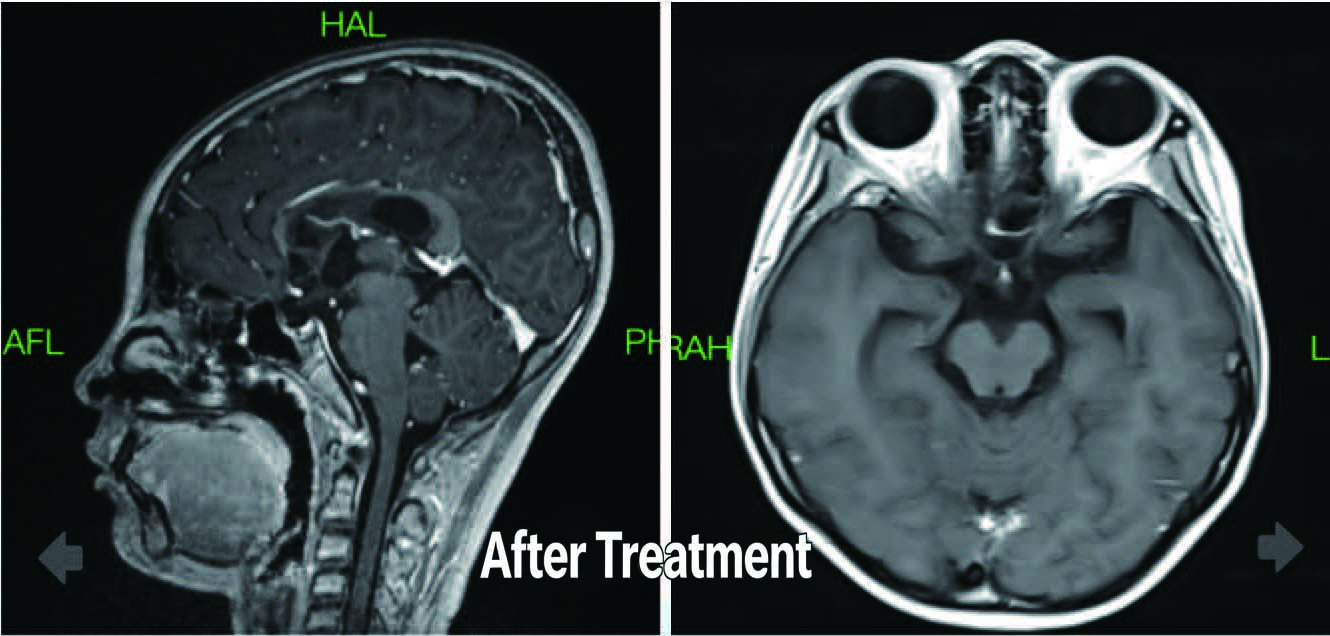

After Treatment

Patient: Female, 16 years old

Diagnosis: Malignant Brain Tumor (lntracranial Germ Cell Tumor, WHO Grade IV)

Symptoms: Intermittent dizziness, dry mouth, thirst, polyuria

Treatment:Started TOMO radiotherapy on May 19, 2022

Radiation dose to PTV: 45 Gy in 25 fractions (1.8 Gy per fraction)

Outcome:Follow-up imaging 10 months later showed a significant reduction in tumor size in the saddle and pineal regions compared to previous scans.